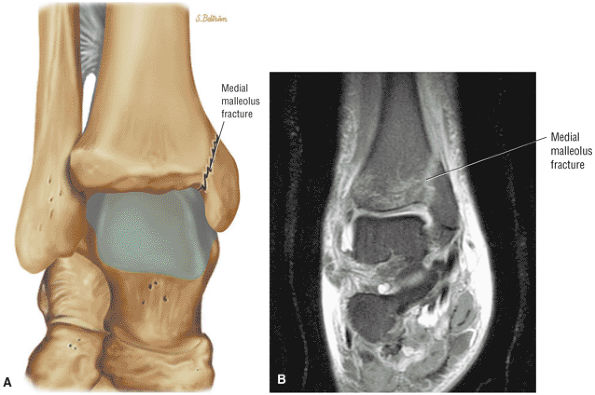

![]() |

|

FIGURE 5.28 Tibiotalar Joint.

FIGURE 5.29 Impingement.